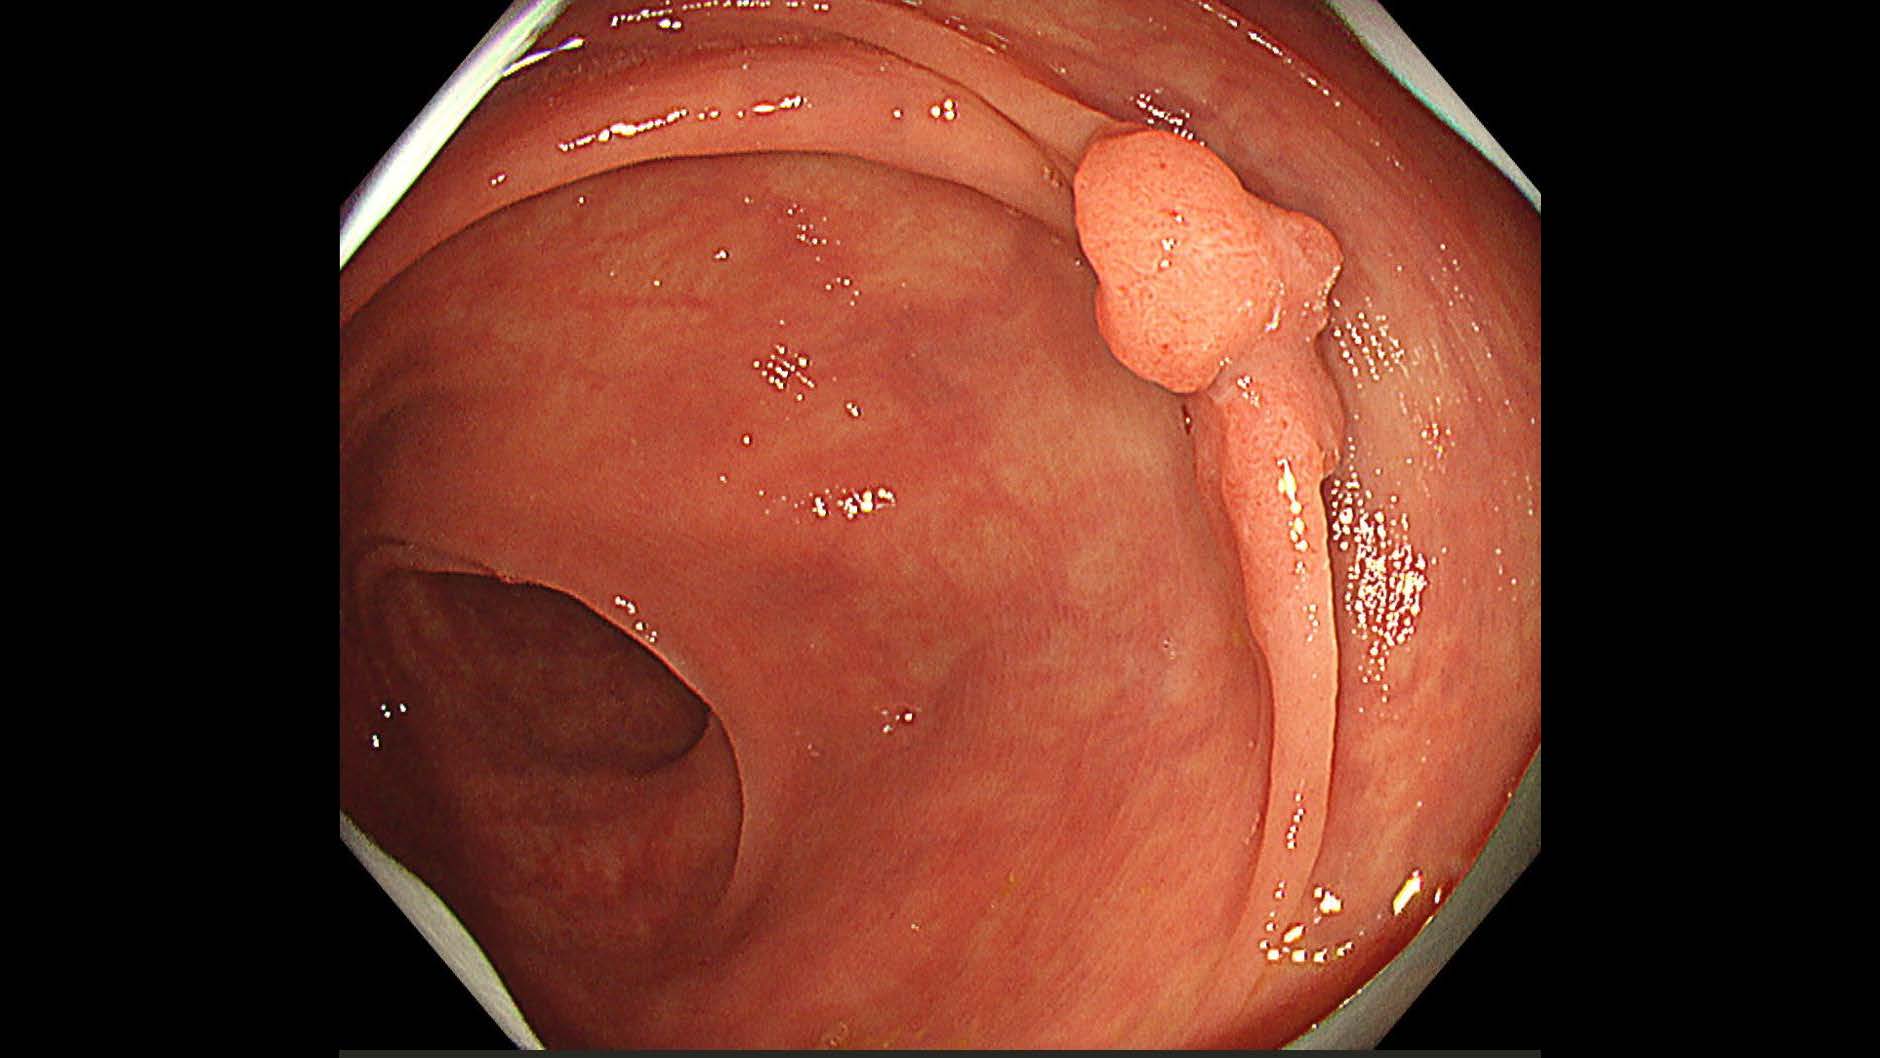

消化管Mapping~大腸~ 2025.6.11

消化管Mapping~大腸~

消化器内科

内視鏡検査・治療

消化管Mapping